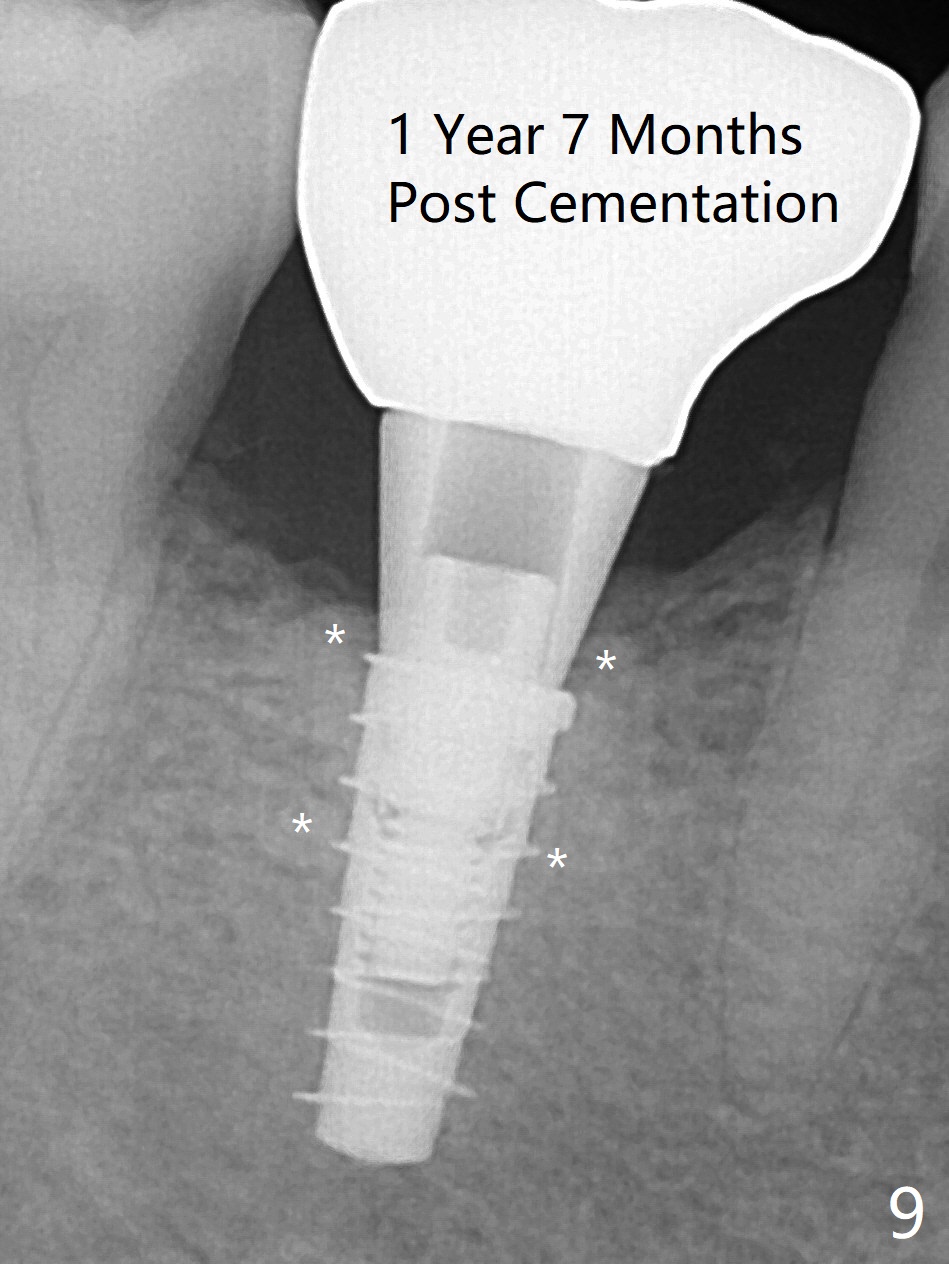

The retained deciduous tooth (lower right 2nd molar, Fig.1 T) has buccal apical infection and recession. After extraction, the initial depth of osteotomy is 11 mm over the flat socket bottom (Fig.2) without visible Mental Loop. Following 3.8 mm Magic Drill for 11 mm, a 4x11 mm dummy implant is placed partially due to hard bone; it appears that the apical osteotomy (Fig.3 yellow outline) overlaps the Mental Loop (red dashed line). For safety, a 4x9 mm IBS implant is placed with insertion torque 40 Ncm; a 5x5.7(4) mm abutment is immediately placed for an immediate provisional to cover the large socket and keep Vera graft in place (Fig.4 *). There is no postop paresthesia, probably due to the fact that the osteotomy is lingual to the Mental Loop. The provisional remains in place 7 days postop; its margin (Fig.5 arrow) covers the socket. The margin of the provisional is trimmed 1 month postop. Impression is taken nearly 3 months postop (Fig.6). The buccal plate looks atrophic 3 months postop (Fig.7 (immediately before cementation)), although there is no sign of periimplantitis. In the future, insert the immediate provisional inside of the buccal gingiva to make the buccal gingiva look bulky instead of buccal to it (Fig.5). The second drawback of placing an implant at the deciduous tooth area is that the crown is wide mesiodistally if orthodontic treatment is not rendered. Although there is lower anterior crowding, the patient declines orthodontic treatment. The bone density around the implant increases 7 months post cementation (Fig.8 *). The higher density bone seems to extend coronally 1 year 7 months post cementation (Fig.9). The dense bone apparently extends toward the abutment as well 3 years 5 months post cementation (Fig.10 curved arrows).